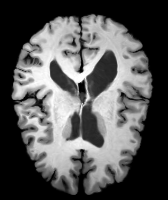

Moving Target Mono-0 Mono-21 DA-1 DA-21 Mono-65 Refer to caption Refer to caption Refer to caption Refer to caption Refer to caption Refer to caption Refer to caption Refer to caption Refer to caption Refer to caption Refer to caption Refer to caption Refer to caption Refer to caption

Figure 4: Examples of brain MRI registration (top) and knee MRI segmentation (bottom) results. Top: The first two columns are the moving image/segmentation and the target image/segmentation followed by the warped moving images/segmentations by different models. Bottom left to right: original image, manual segmentation, and predictions of various models. Mono-i𝑖i and DA-i𝑖i represent the mono- and DA models trained with i𝑖i manual segmentations respectively.

Brain MRI experiment: We also evaluate our method on the MindBooggle101 [4] brain MRIs with 32 cortical regions. We fuse corresponding segmentation labels of the left and right brain hemispheres. MindBoogle101 consists of images from multiple datasets, e.g., OASIS-TRT-20, MMRR-21 and HLN-12. After removing images with incorrect labels, we obtain a total of 85 images. We use 5 images from OASIS-TRT-20 as validation set and 15 as test set. We use the remaining 65 images for training. Manual segmentations in the N=1 and N=21 experiments are only from the MMRR-21 subset; this simulates a common practical use case, where we only have few manual segmentations for one dataset and additional unlabeled images from other datasets, but desire to process a different, new dataset. All images are 1mm isotropic, affinely-aligned, histogram-matched, and cropped to size 168×200×169168200169168\times 200\times 169. We apply sagittal flipping for training data augmentation. We use the same loss weights as for the knee MRI experiment except for λr=5,000subscript𝜆𝑟5000\lambda_{r}=5,000, since cross-subject brain registrations require large deformations and hence less regularization.

Brain results: Dice scores for segmentation and registration increase by about 2.6 and 3.5 respectively for the cortical structures of the brain MRIs.